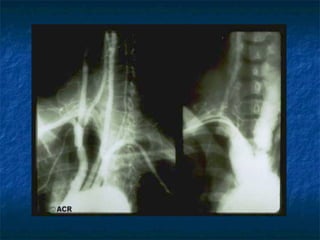

TAKAYASU ARTERITIS                                                      Inflamación granulomatosa de la aorta y sus ramas principales. Usualmente ocurre en pacientes menores de 50 años.